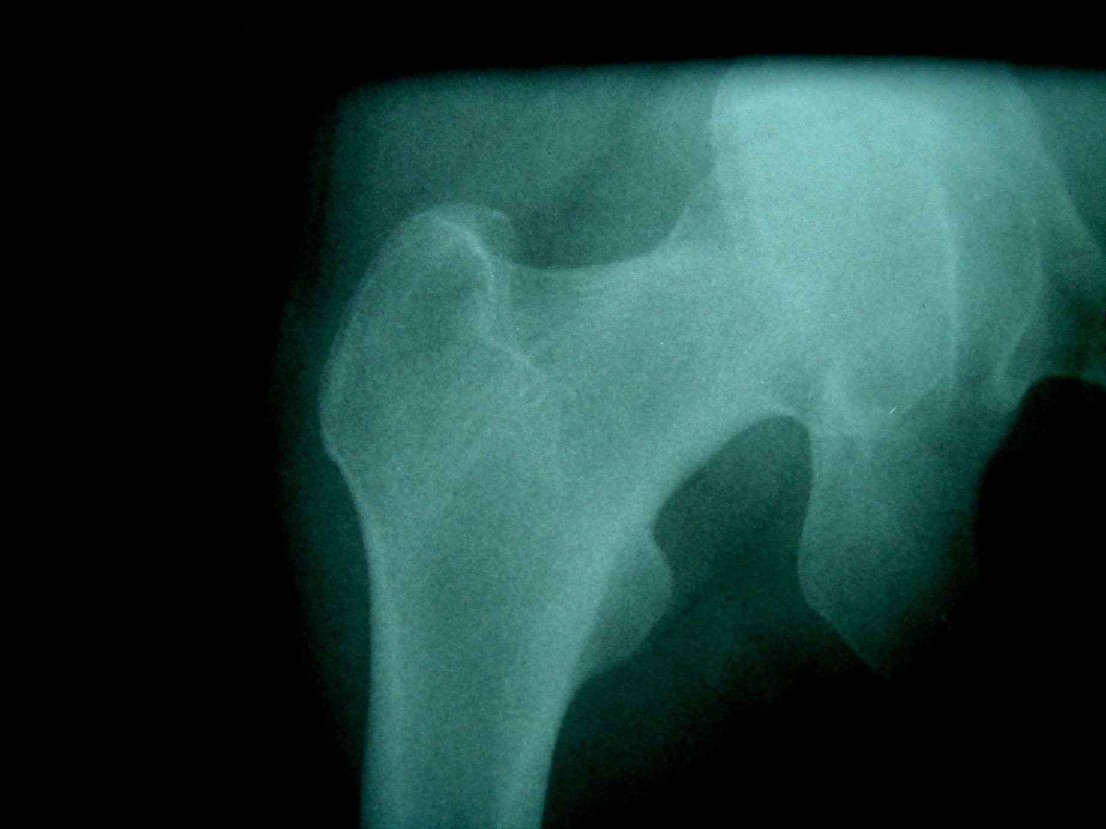

患者,女,因外伤就诊。摄骨盆及右股骨。当时报告骨盆未见明显异常,右股骨中段粉碎性骨折。五天后行股骨中段骨折内固定手术,术中摄床边片示股骨颈骨折。现把术前和术中图像上传。请大家高诊,分析股骨颈骨折是术前漏诊还是其他原因。术前骨盆片右股骨颈显示欠佳是由于股骨中段骨折无法将股骨颈完全显示。

术前片示右股骨颈未见明显骨折征象。如果事先有骨折,由于投照位置原因,骨折线也是完全有可能被挡住重叠而看不见的(并且本例骨折对位良好,更有可能看不到)。所以要凭此判断述前是否有骨折不容易

从上传的照片来看,术前无法诊断骨折。可能是投照角度的问题。

由于术前下段骨折 股骨颈显示不完全所致 很正常啊

术前股骨颈未见骨折

当然可能由于术前骨折对位对线良好,有可能观察不到骨折线,有的裂纹骨折平片当时是看不见骨折线的,7天左右才可能由于骨折线水肿&活动等原因从而显示出骨折线;还有投照位置的原因。术前未看见骨折线也属正常现象。

考虑术前骨折(由于投照位置原因,骨折线有可能被挡住重叠而看不见的或骨折处未有移位可能看不到)。术后由于外力作用骨折线增宽而清楚显示)。

术前由于位置原因使股骨颈未全部显示,骨折线与股骨头重叠,骨折也可以使股骨颈缩短

回头看术前片,可见一低密透光区.

术前所照的片子体位好象有点不标准,右侧股骨颈显示不是很好,没有完全展开,所以不好说术前就一定没有骨折的情况.

楼主给我们大家提供了非常好的片子,感谢!该片股骨颈的骨折术前看不到骨折。这个和体位也有关,但是我们都知道,那些标准的体位是给健康人设计的,外伤比较重的往往都无法标准投照。不知道同行们有没有这样一种感受:发现明显的问题了,就心里比较踏实了,舒坦了,就不容易对其它细节仔细观察了。如果没有发现明显的问题,就仔细的翻来覆去的看。所以这个片子给我们很大的教训:仔细阅片!即便是已经发现问题了。如果非要给鸡蛋里面挑骨头,我认为楼主忽略了右髋关节囊的肿胀,诊断报告应该提一下。外伤的病人我最怕股骨颈的漏诊,一般我都要看软组织。我是一个小医院的,我深有感触,发现骨折不是功劳,而漏诊却是事故,还遭受别人耻笑:放射科的连骨头断没断都看不出来!

关于楼主说的骨折线的形态,的确和一般外伤的有种不太一样的感觉,上方裂隙较明显,下方骨皮质“连续”,我认为成年人应该是全部断了的,不全骨折的可能性非常非常小,该片恰好无法全部显示骨折线。骨折线的形态不能判定术前还是术后骨折。以上只是个人小小看法,请各位老师指正为谢!